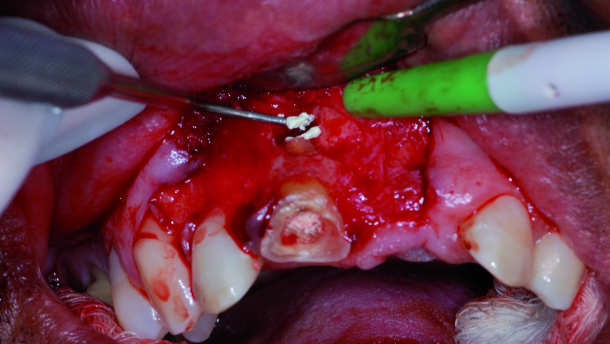

This case illustrates the use of MTA for sealing the root perforation and the effectiveness of the retrofilling material after apicectomy (additional surgery; Figs. 1–17). A 51-year-old patient presented to the Universidade Tuiuti do Paraná dental clinic (Brazil) complaining about a gap in the gingiva above tooth #11, from which a large quantity of purulent discharge was draining. In the radiographic examination, an extensive radiolucent area was found, indicating a fistula (periapical lesion) involving the periapical region of the tooth in question.

During the endodontic treatment, the secretion into the tooth could not be controlled. Even 23 days after treatment, with changes to the intra-canal medication, the fistula returned and the exudates drainage via the canal persisted. Definitive sealing of the root perforation was then opted for, utilizing MTA and continuing with changes of calcium hydroxide in the root canal. Owing to the persistence of the exudate via the canal, it was decided to perform endodontic filling, followed by supplementary surgical treatment (apicectomy) with retro-filling with MTA, conserving the tooth structure as much as possible.

The surgery was performed under local anaesthetic with an infraorbital nerve block and supplementary infiltrative anaesthesia at the apex of the tooth, as well as a nasopalatine nerve block. The anaesthesia used was 3 % mepivacaine with 1:1,000,000 adrenaline.

The incision was made with a #15 scalpel blade and a flap was raised. The osteotomy was performed with a high-rotation drill of the 700 series in order to gain access to the periapical region. The lesion was curetted with a short curette. An apicectomy was performed with the drill and 2 mm of the apex was removed. The cavity for retro-filling was prepared with a spherical drill under constant irrigation with saline solution, and then the retro-filling with MTA was performed. After condensation of the material in the cavity, the excess was removed with a periodontal curette. Finally, the flap was repositioned and then sutured.